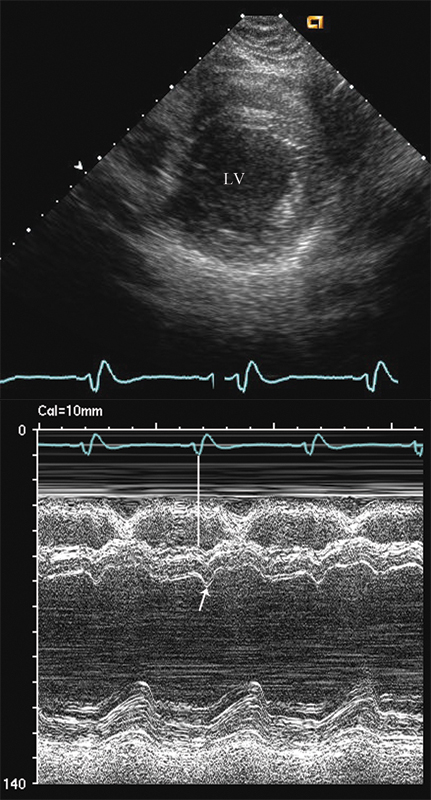

فحوصات تشخيصية لبعض امراض القلب والشرايين التاجية